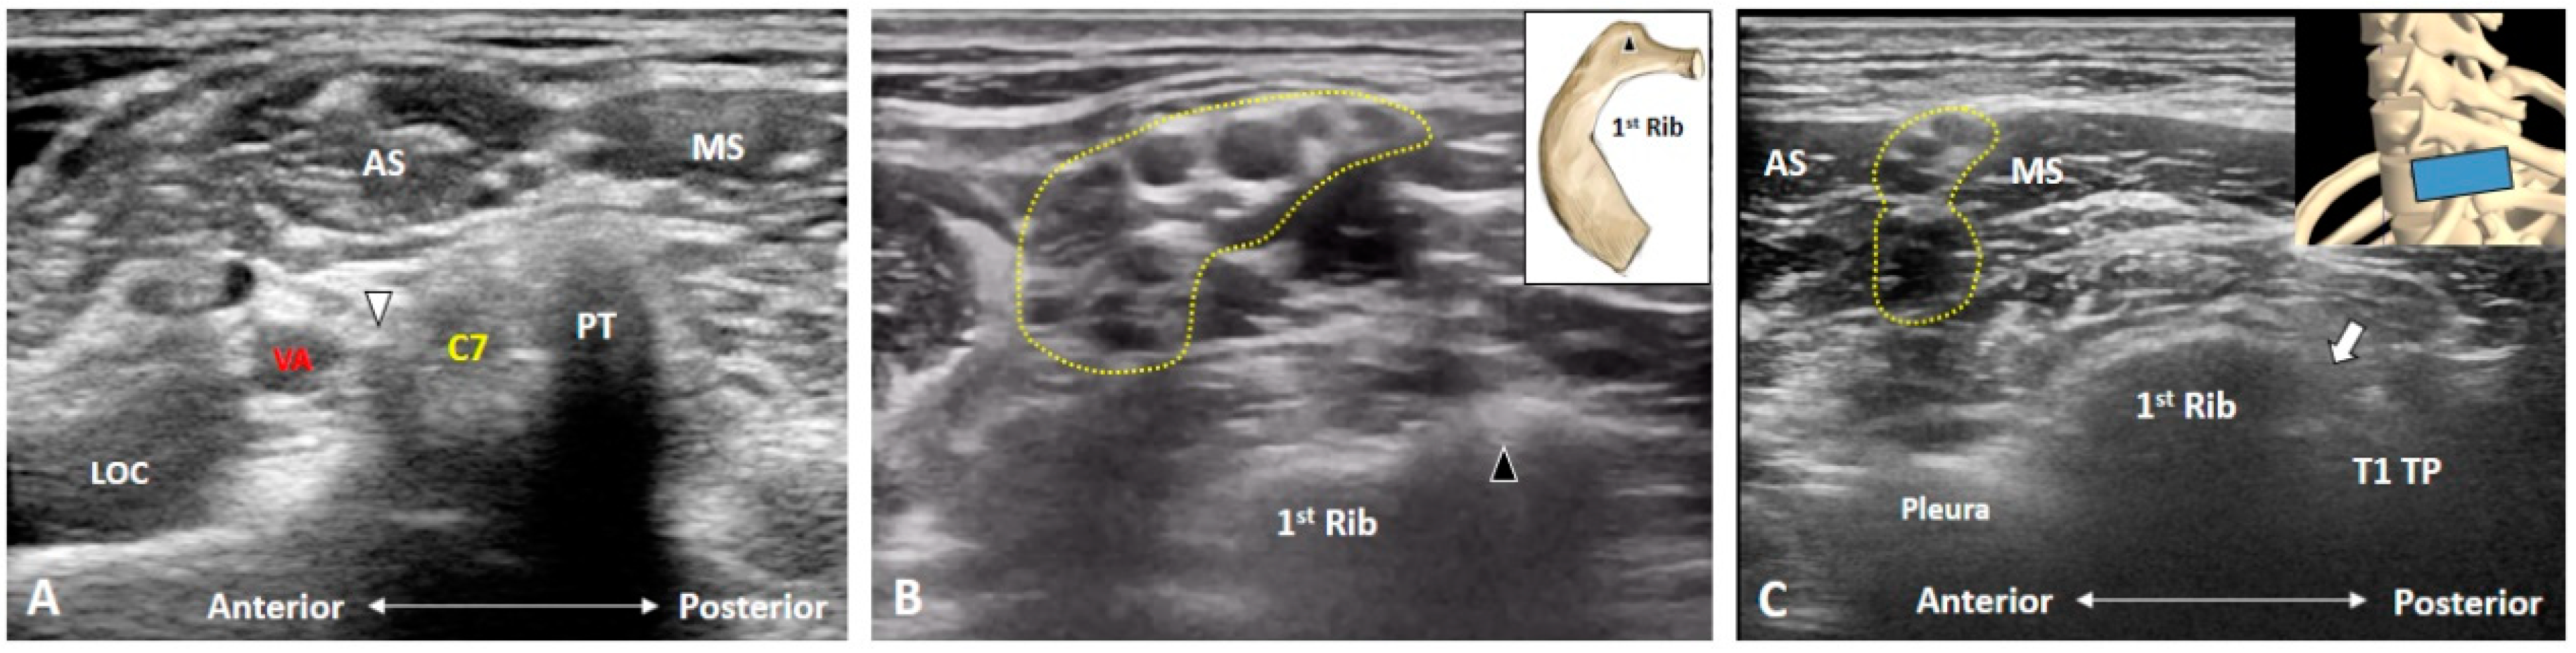

3.2. Is the C7 Transverse Process Easily Recognized?

3.3. How Can We Locate the C8 and T1 Roots?

3.4. How Can We Better Visualize Cervical Anterior Rami during the Scanning Process?